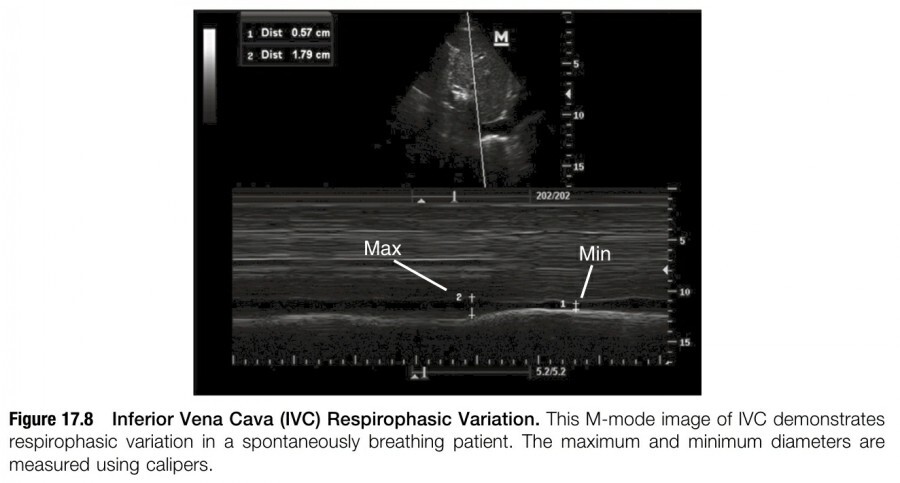

Respiration cycle 동안 IVC diameter의 variation을 확인하기 위해 M-mode를 사용할 수도 있다(figure 17.8). IVC가 증가한 것으로 잘못 판단하는 것을 피하기 위해서 M-mode sampling plane이 IVC에 수직으로 위치하는 것을 확인해야 한다.